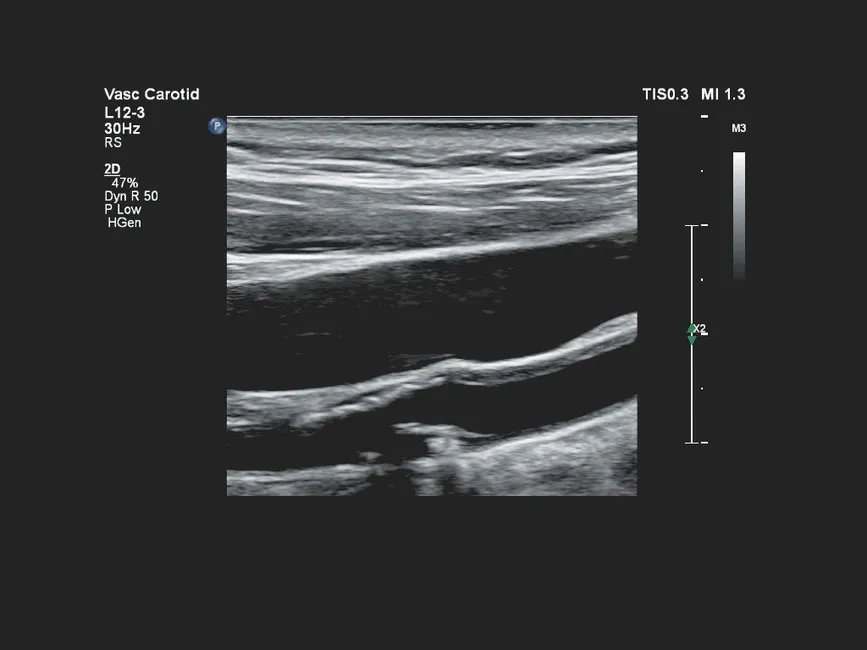

| L12-3 | 3–12 | Broadband линейный датчик | 160 | Сосудистые исследования, исследования мелких органов и поверхностных структур |

- Сосудистые исследования артерий и вен (периферические, шейные, внутрибрюшные сосуды).